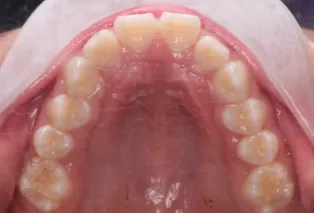

Photos intra-orales